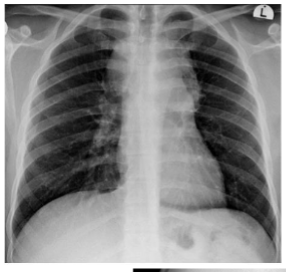

what is this?

multifactorial pna